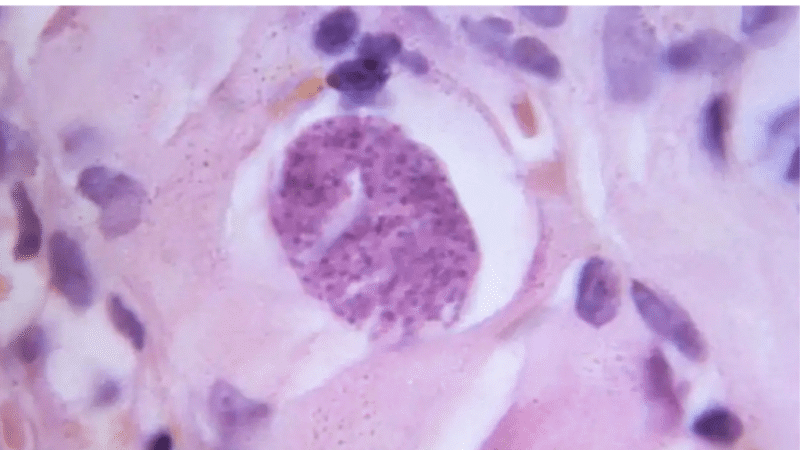

En la mayoría de las personas sanas, la infección no produce síntomas evidentes. Tras la fase inicial, el parásito forma quistes tisulares en órganos como el cerebro, los músculos y el corazón. Durante años, estos quistes se consideraron estructuras completamente inactivas.

Sin embargo, el estudio publicado en Nature Communications en 2026 demostró que esta idea era incompleta. Los investigadores hallaron que los quistes no son homogéneos, sino que albergan diversos subtipos del parásito, cada uno con funciones y comportamientos distintos.

La investigación liderada por Emma H. Wilson y su equipo utilizó secuenciación de ARN unicelular en modelos animales para analizar el contenido interno de los quistes de Toxoplasma gondii. El resultado fue inesperado: dentro de un solo quiste coexisten múltiples formas del parásito.

Algunos subtipos mostraron señales de actividad metabólica, mientras que otros parecían estar más cerca de reactivarse. Esto indica que el quiste no es un refugio pasivo, sino un centro dinámico donde el parásito toma decisiones clave sobre su desarrollo.